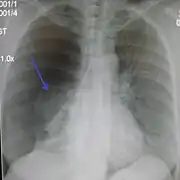

Chest X-ray

A plain chest radiograph, ideally with the X-ray beams being projected from the back (posteroanterior, or "PA"), and during maximal inspiration (holding one's breath), is the most appropriate first investigation.[30] It is not believed that routinely taking images during expiration would confer any benefit.[31] Still, they may be useful in the detection of a pneumothorax when clinical suspicion is high but yet an inspiratory radiograph appears normal.[32] Also, if the PA X-ray does not show a pneumothorax but there is a strong suspicion of one, lateral X-rays (with beams projecting from the side) may be performed, but this is not routine practice.[15][19]

Lateral inspired X-ray at the same time, more clearly showing the pneumothorax posteriorly in this case

Anteroposterior expired X-ray at the same time, more clearly showing the pneumothorax in this case

Chest X-ray showing a pneumothorax on the right (left in the image), where the absence of lung markings indicates that there is free air inside the chest

Chest X-ray showing the features of pneumothorax on the left side of the person (right in image)

It is not unusual for the mediastinum (the structure between the lungs that contains the heart, great blood vessels, and large airways) to be shifted away from the affected lung due to the pressure differences. This is not equivalent to a tension pneumothorax, which is determined mainly by the constellation of symptoms, hypoxia, and shock.[13]

The size of the pneumothorax (i.e. the volume of air in the pleural space) can be determined with a reasonable degree of accuracy by measuring the distance between the chest wall and the lung. This is relevant to treatment, as smaller pneumothoraces may be managed differently. An air rim of 2 cm means that the pneumothorax occupies about 50% of the hemithorax.[15] British professional guidelines have traditionally stated that the measurement should be performed at the level of the hilum (where blood vessels and airways enter the lung) with 2 cm as the cutoff,[15] while American guidelines state that the measurement should be done at the apex (top) of the lung with 3 cm differentiating between a "small" and a "large" pneumothorax.[33] The latter method may overestimate the size of a pneumothorax if it is located mainly at the apex, which is a common occurrence.[15] The various methods correlate poorly but are the best easily available ways of estimating pneumothorax size.[15][19] CT scanning (see below) can provide a more accurate determination of the size of the pneumothorax, but its routine use in this setting is not recommended.[33]